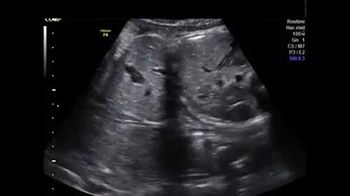

Challenge your diagnostic skills: Is everything normal in this fetal abdomen?

Challenge your diagnostic skills: Is everything fine with this third trimester pregnancy?